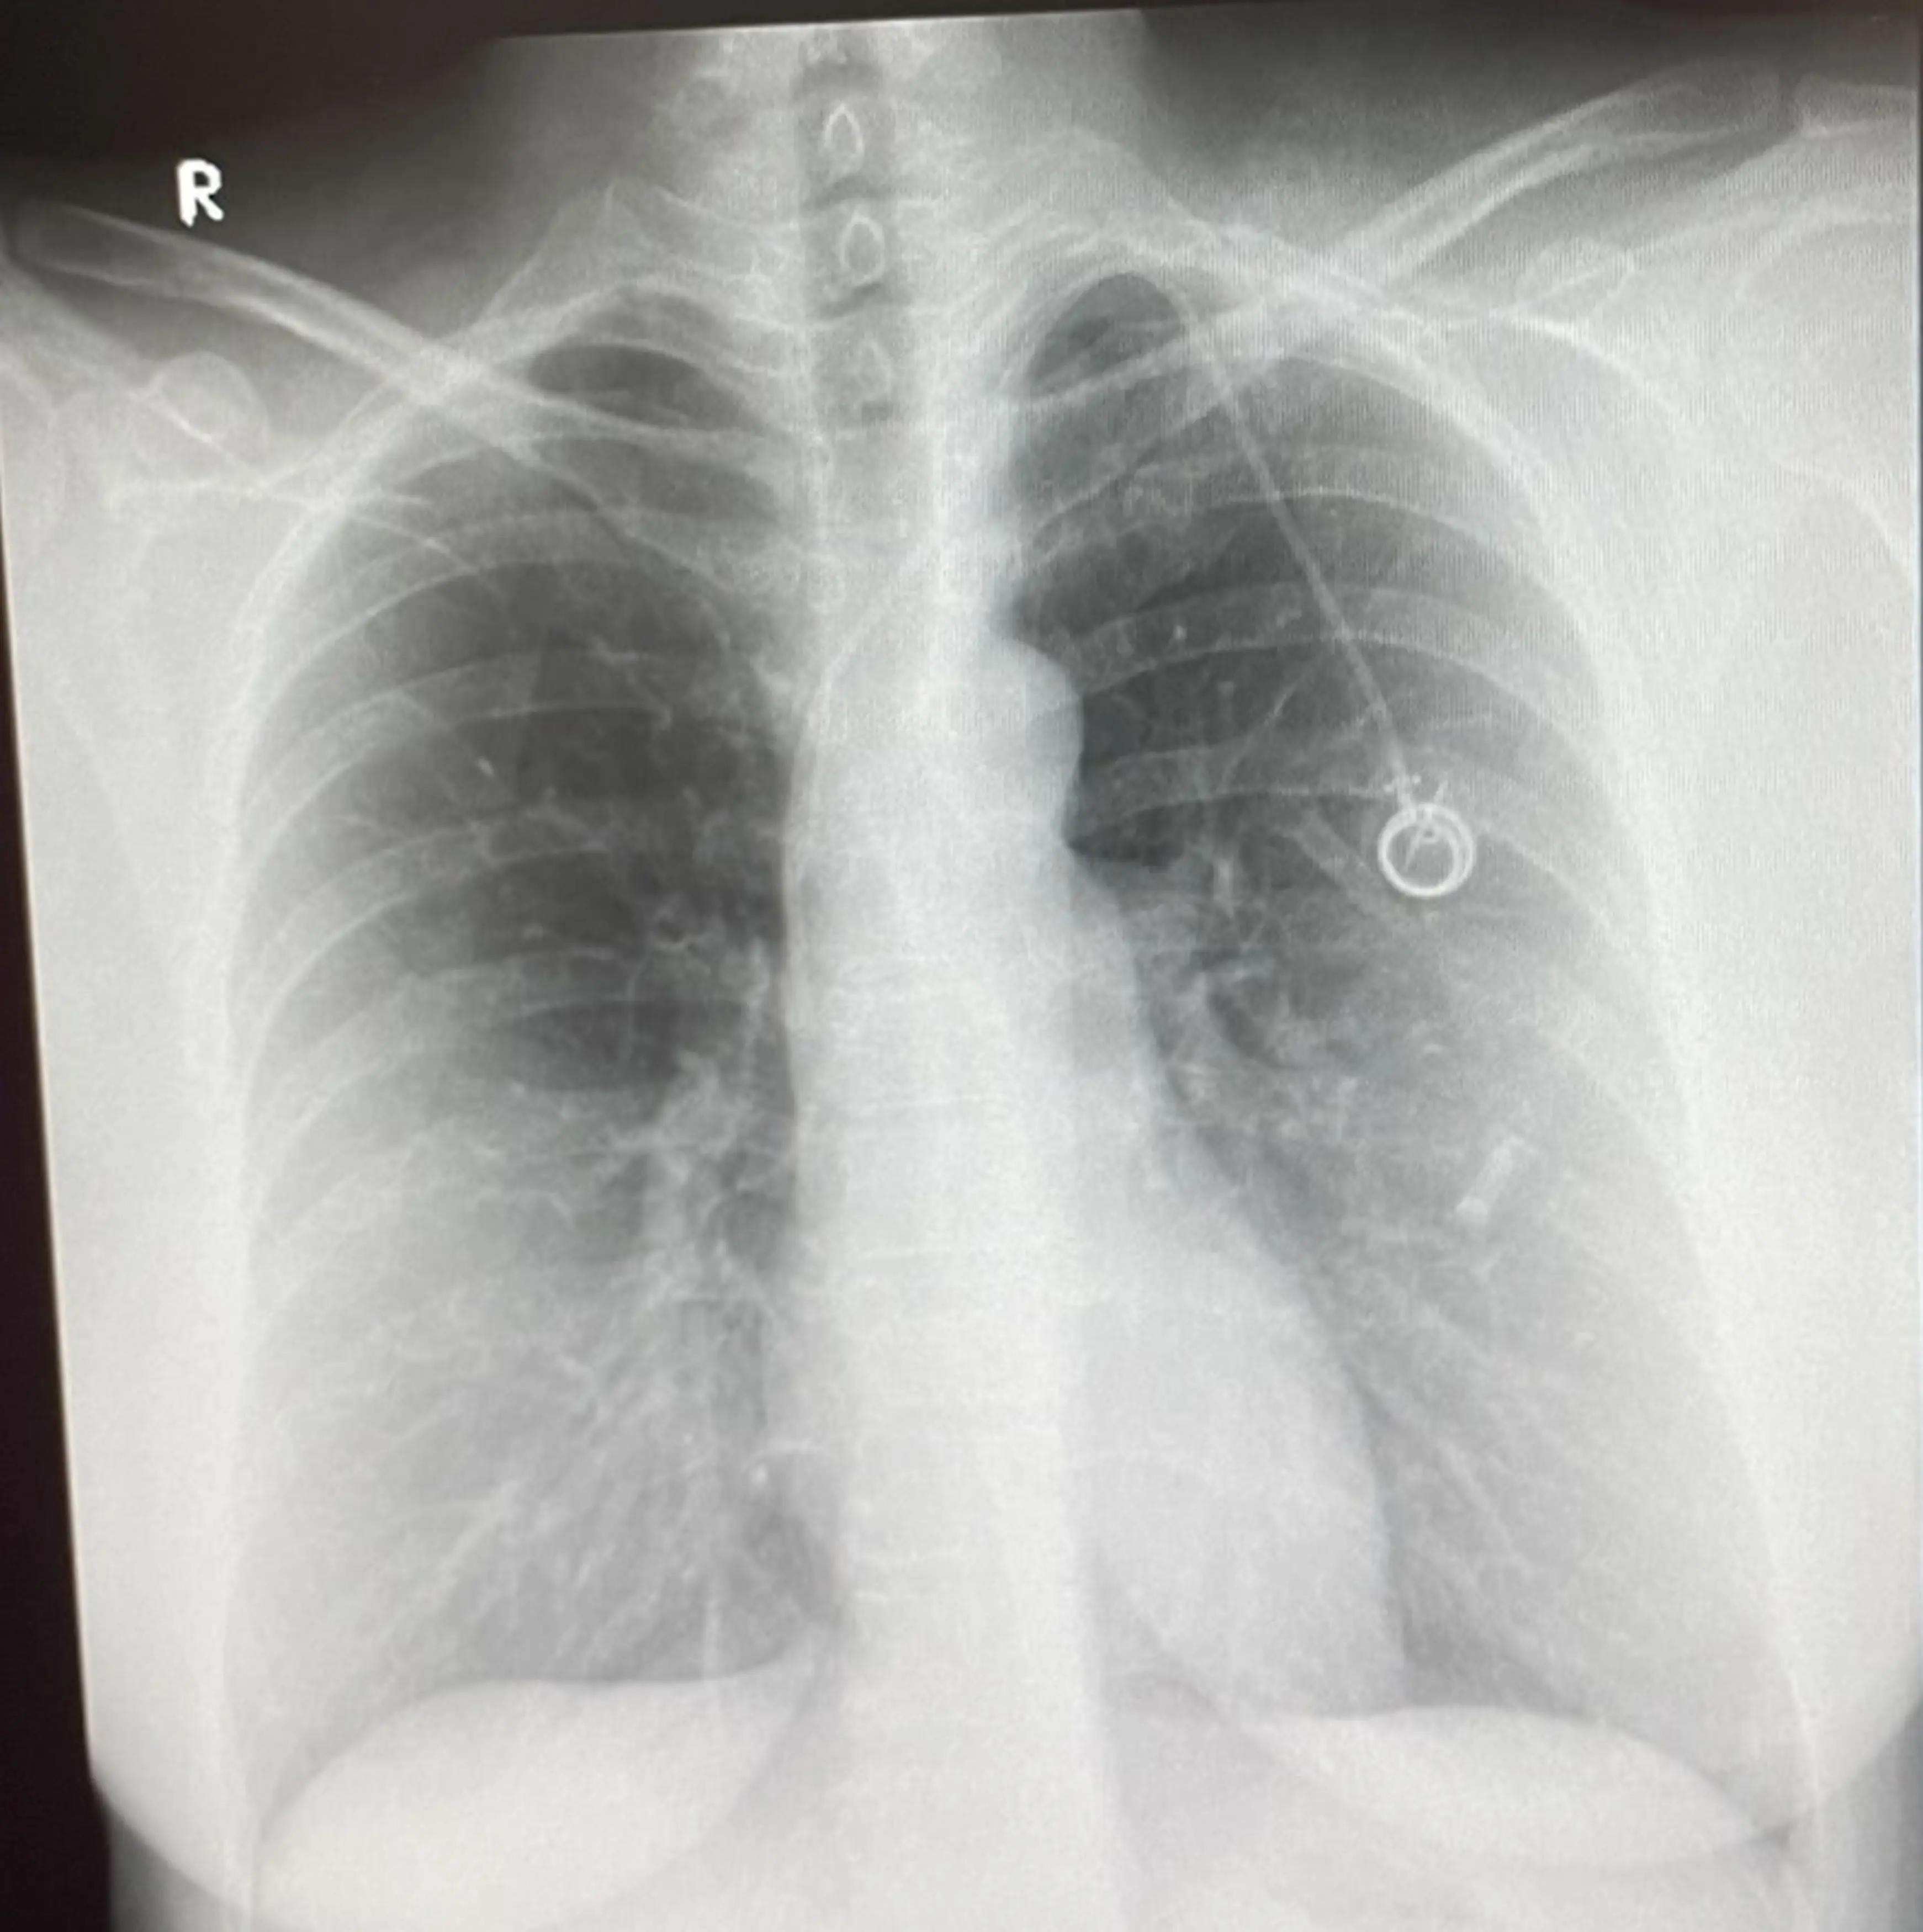

It was there that she was immediately referred to a breast clinic, where she underwent both a mammogram, and two painful biopsies.

Two days later, she was dealt the life-changing blow - she had triple negative breast cancer, which had already spread to her bones and liver.

"I went for a full body CT scan and was told the cancer has spread to my liver and bones too, which is classed as stage four.